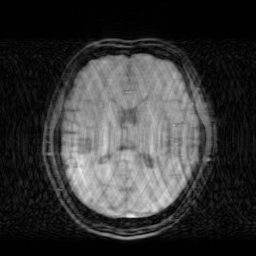

We illustrate with reconstructions for three CS-MRI methods: TLMRI (transform learning MRI) [25], PANO (patch-based nonlocal operator) [23] and GBRWT (graph-based redundant wavelet transform) [14]. The PANO and GBRWT models achieve impressive reconstruction qualities because they use an nonlocal prior and adaptive graph-based wavelet transform to exploit image structures. In TLMRI, the sparsifying transform learning and the reconstruction are performed simultaneously in more efficient way than DLMRI [24]. The three methods represent the state-of-the-art performance in the non-deep CS-MRI models. In Figure 2, we show the reconstructions error for zero-filled (itself a potential reconstruction “algorithm”), TLMRI, PANO and GBRWT on a complexed-valued brain MRI using 30%percent3030\% Cartesian under-sampling. The error display ranges from 0 to 0.2 with normalized data. The parameter setting will be elaborated in the Experiment Section V.

We also consider the deep learning DC-CNN model [26] as the guide module. We also give the reconstruction error in Figure 2. We observe the zero-filled, TLMRI, PANO, GBRWT and DC-CNN models all suffer the structural reconstruction errors, while the DC-CNN model achieves the highest reconstruction quality with minimal errors because of its powerful model capacity. Another advantage of this CNN model is that, once the network is trained, testing is very fast compared with conventional sparse-regularization CS-MRI models. This is because no iterative algorithm needs to be run for optimization during testing since the operations are a simple feed forward function of the input. We compare the reconstruction time of TLMRI, PANO, GBRWT and DC-CNN for testing for Figure 2 in Table I.

Figure 2: The reconstruction error of a brain MRI using zero-filled, TLMRI, PANO, GBRWT and DC-CNN under 1D 30%percent3030\% under-sampling mask.